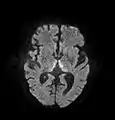

صورة محورية تظهر إشارة تدل على انتشار محدود في الوسط المهادي الظهري.

صورة محورية عن طريق الرنين المغناطيسي FLAIR تظهر إشارة في الوسط المهادي ظهري ، وهو شيء شائع في الاعتلال الدماغي المرتبط بمتلازمة فيرنيك. كان هذا المريض تقريبا في حالة غيبوبة عندما بدأ تمديده بالثيامين وريدياً ، استجاب بشكل جيد لكنه ترك بعض العجز المرتبط بمتلازمة كورساكوف.